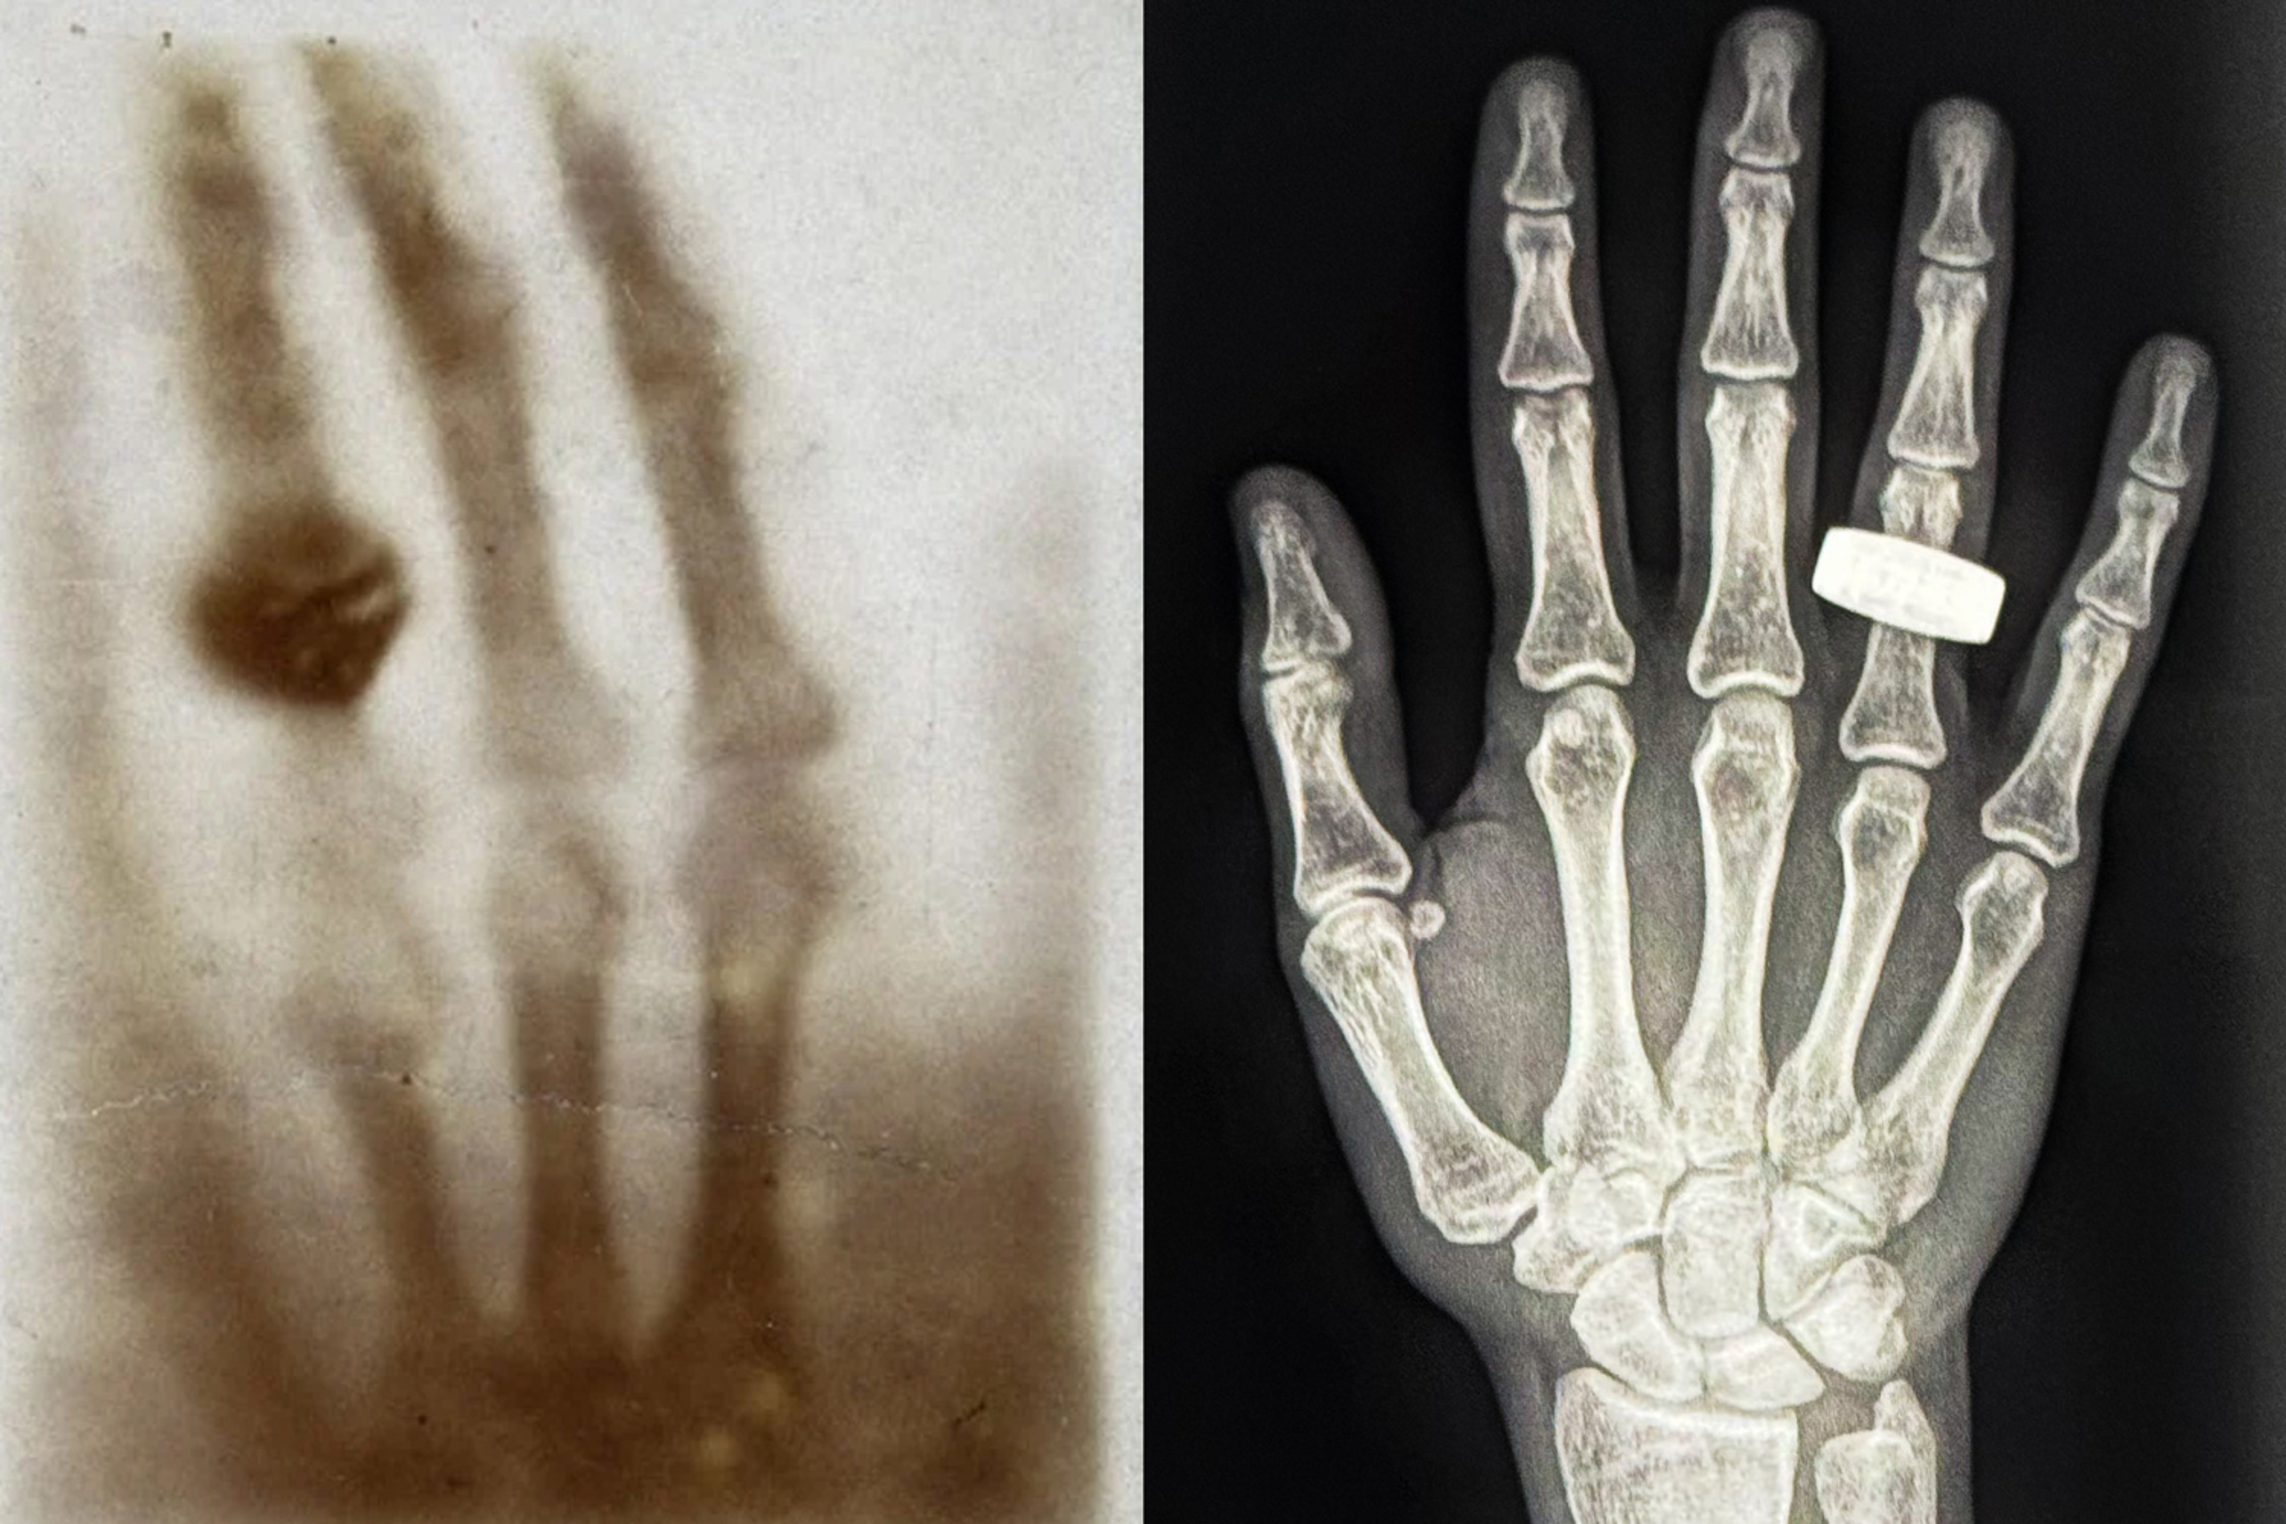

Last week, crew members aboard the Fram2 mission posted to social media and shared the first-ever medical X-ray image taken in space. The image is a black-and-white scan of a hand with a ring, echoing the very first X-ray image ever taken, 130 years ago, by the physicist Wilhelm Roentgen, of his wife’s hand. The new X-ray image was taken in microgravity, inside a four-person space capsule flying at orbital speeds of 17,500 miles per hour, about 200 miles above the Earth’s surface.

The body scans are a first demonstration that medical X-ray imaging can be done within the confines and conditions in space. Lonnie Petersen, a co-investigator on the SpaceXray project, is an associate professor in MIT’s Department of Aeronautics and Astronautics who studies space physiology and the effects of spaceflight on the human body. Petersen helped to define and design the protocol around the SpaceXray project, in collaboration with institutional partners such as Stanford University and the Mayo Clinic, and X-ray hardware companies KA and MinXray. Petersen talked with MIT News about how these first in-orbit X-ray images can help enable safe and healthy longer-term missions in space.

In terms of methods, one of my concerns was that the increased background radiation might reduce the quality of the image so that it would fall below clinical standards. From the first images we have received from space, it seems that the quality is great. I am very excited to further analyze the full set of images.

A: The crew learned how to take X-rays in one afternoon. It was done as a train-the-trainer model. The protocol was created in advance and the crew took images of each other, checked the quality, and stored the images. We have only seen one image so far, but from that, we are very impressed with the quality, the skills, and the dedication to advancing science by the crew.